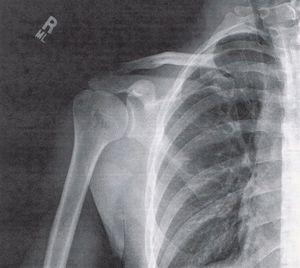

Данный синдром характеризуется возникновением болей и нарушением работы плечевого сустава при выполнении определённых движений. Это связано с сжатием сустава и окружающих его сухожилий, что вызывает проявление симптомов заболевания.

Болевые ощущения возникают при движениях, связанных с вращательной манжетой плеча и акромионом. Поэтому данное состояние также называют синдромом сжатия ротатора плеча или синдромом компрессии сухожилия надостной мышцы плеча.